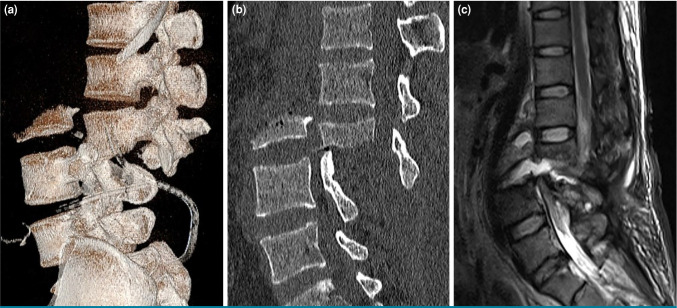

Severe old lumbar fractures and dislocations with associated cauda equina nerve transection are rare clinical presentations which pose significant management challenges. This case report highlights a unique instance of such an injury, emphasizing novel surgical strategies for reconstruction and recovery. A 30-year-old male patient was admitted after sustaining a severe open fracture and degree IV posterior dislocation of L3 vertebra, accompanied by cauda equina nerve transection, spinal cord injury and multiple organ injuries. Following initial stabilization, the patient underwent surgical reduction and internal fixation two months after the injury. The procedure involved cauda equina nerve reconstruction using sural nerve grafts. Postoperatively, the patient showed improved bladder function and regained some mobility. However, he later developed arachnoiditis ossificans of the cauda equina, resulting in severe pain, which required additional surgical intervention. In conclusion, this case underscores the importance of timely intervention in severe thoracolumbar injuries and presents a successful approach to nerve reconstruction.